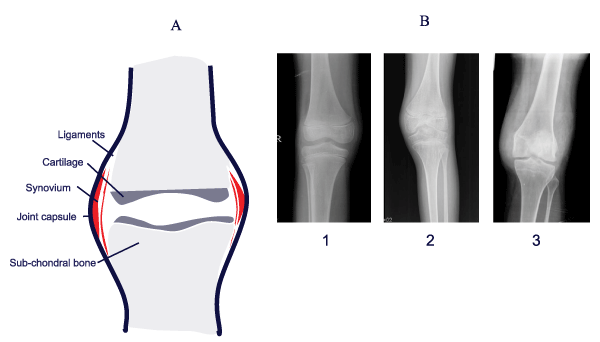

| Figure 2: (A) Joint architecture: Synovial tissue: synthesizes synovial fluid, nourishes and lubricates the articular cartilage, enabling smooth movement of the joints. The synovial tissue has a synovial lining and the sublining. The synovial lining is composed of Macrophages (Type A synovial cells) and specialized fibroblasts (Type B synovial cells). The uptake of excess synovial fluid or breakdown products of cartilage is achieved by the synovial tissue. Articular cartilage is avascular, aneural, and depends mostly on the synovial fluid for its nutrition and maintenance. The main function of chondrocytes (sole population of cartilage) is the production and maintenance of extracellular matrix and balancing catabolic processes in the joint space. Blood induced joint damage is widely thought to happen by direct damage to the chondrocyte metabolism and integrity by components of the blood, while the indirect one is attributable to the inflammatory mediators and enzymes released by the inflamed synovium as a result of the blood in the joint cavity. (B) Radiographs of knee joints from normal individual (Panel 1), haemophilic patients with articular damage (Panel 2) and synovitis (Panel 3). |